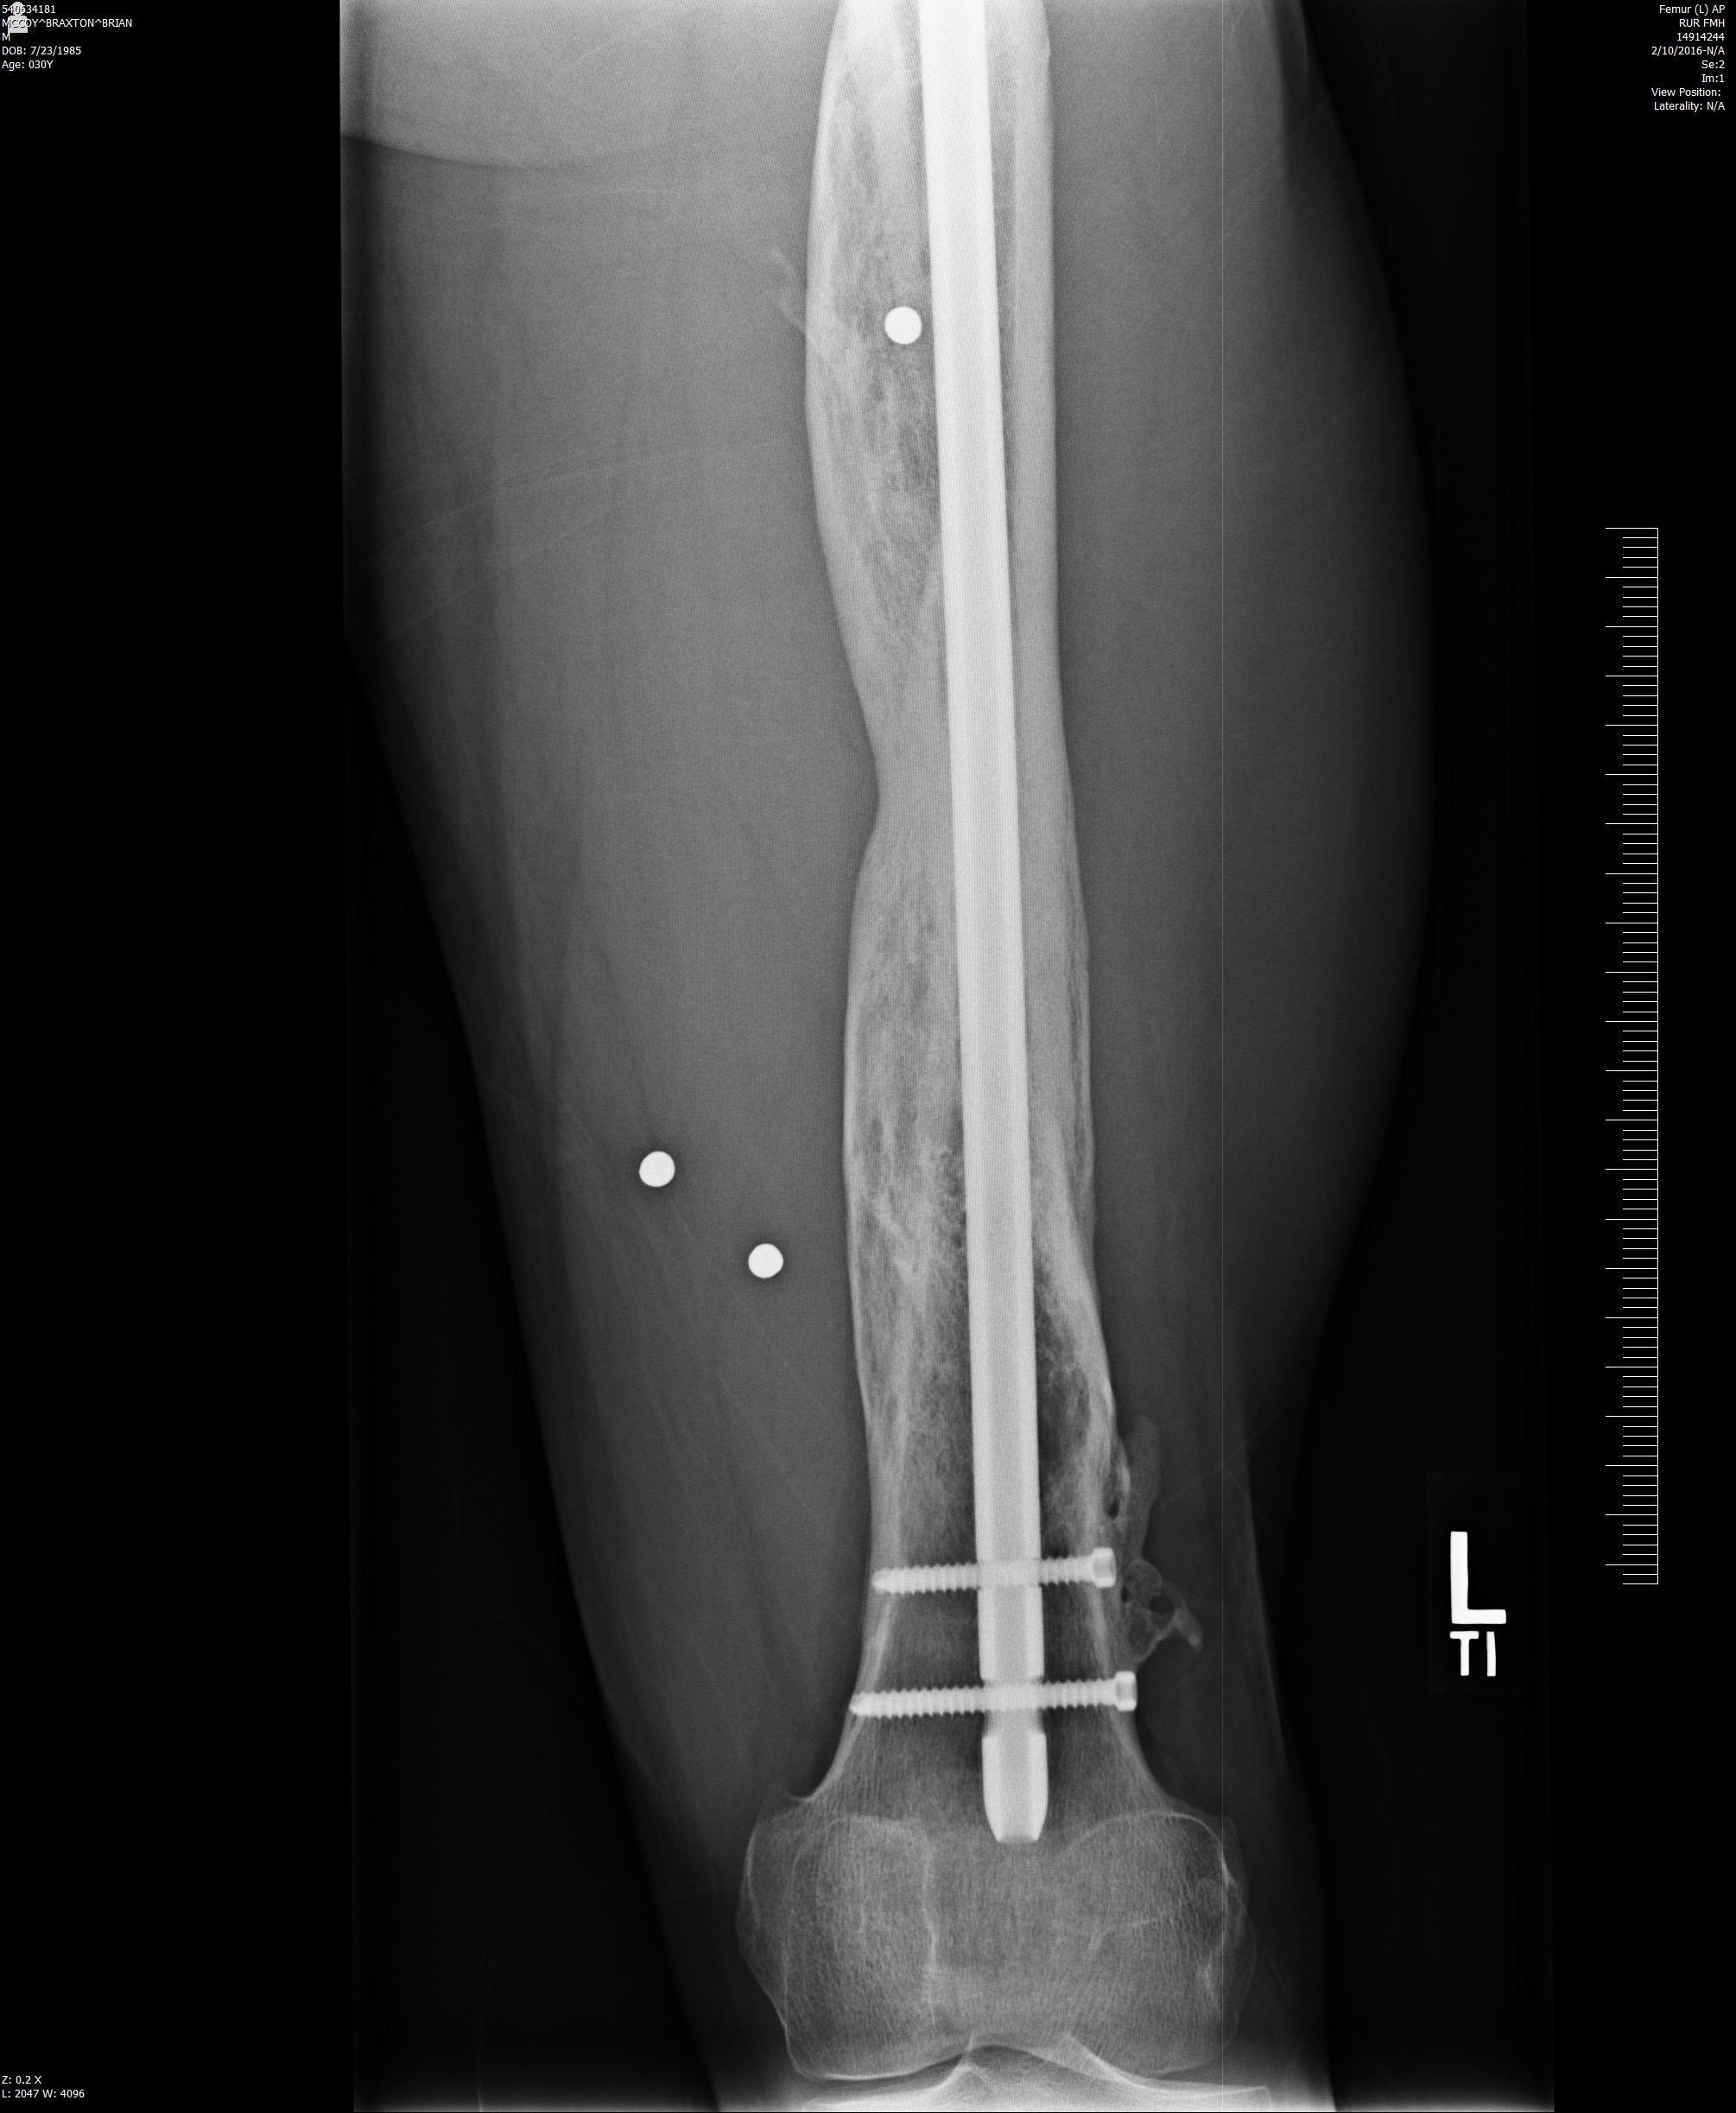

In 2006, Sgt. Braxton McCoy (Ret.) while performing a security detail outside of Ramadi, Iraq, was severely wounded by a suicide bomber. Both his legs and arms were broken in multiple places, spine was fractured, had a number of fractured ribs, had bleeding on the brain, and a severed medial nerve to his right hand.  What followed was over two dozen surgeries and nearly a decade of physical therapy and rehabilitation. It was during his long term recovery, Sgt. McCoy twice served as a National Advocate for the Army Wounded Warrior Program, and twice as Veterans’ Advocate for the Coalition of Iraq and Afghanistan Veterans in the District of Columbia. These four years as an advocate were focused on getting veterans back to work, as a meaningful way to outflank Post Traumatic Stress Disorder.